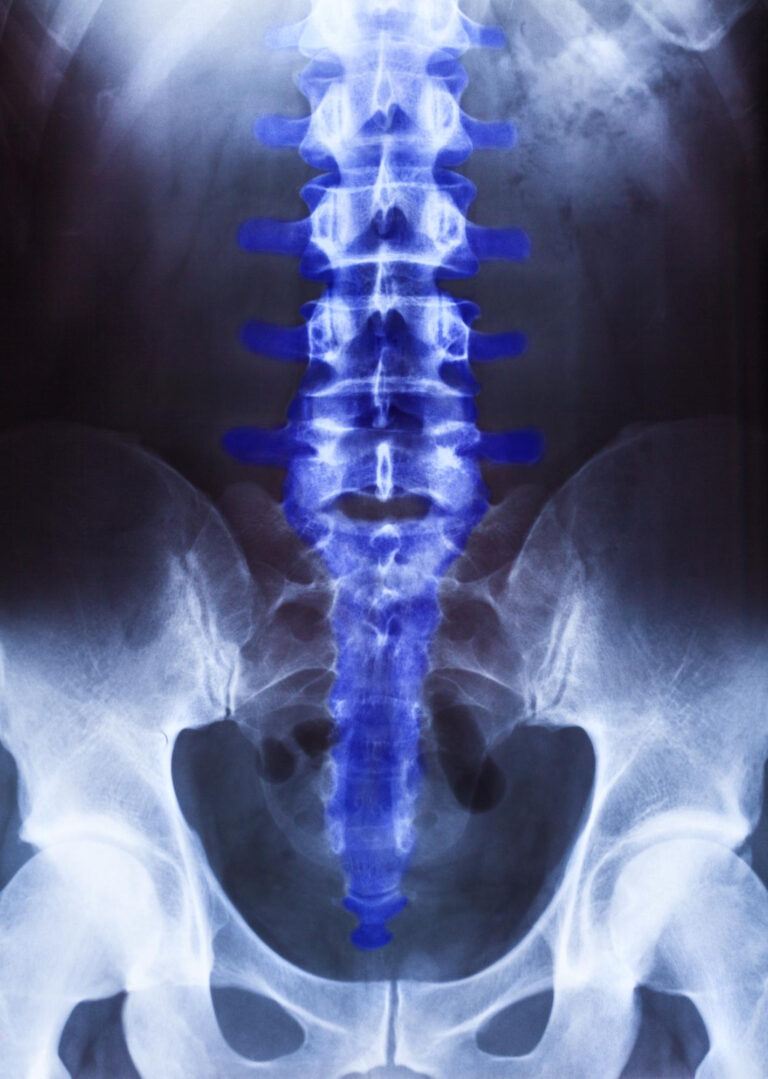

At Dr. O Chiropractic, we provide personalized chiropractic care in McKinney, TX to help you move better, feel better, and live pain-free. Our approach focuses on identifying and correcting spinal misalignments—known as subluxations—that interfere with your body’s natural ability to function and heal.

Understanding Spinal Misalignments

Our chiropractors first evaluate and diagnose the spine to locate any areas of misalignment or “shifts.” These spinal subluxations can create stress on the nervous system, leading to pain, stiffness, or other health issues. Using x-rays, advanced diagnostic tools, and precise palpation techniques, we identify where and how your spine has been affected.

Chiropractic care is rooted in the scientific principle that the nervous system controls and influences every organ, tissue, and cell in the body. When the spine is properly aligned, the nervous system can communicate freely—allowing your body to function optimally, reduce pain, and promote natural healing.

All body functions are controlled by the nervous system. Sometimes the spinal vertebras will get misaligned which will cause pressure on the nerve which will lead you to feel discomfort/pain and even at times radiating pain to wherever the nerve is traveling.

Once the Doctor finds these areas of misalignments the chiropractor will adjust these areas gently using his/her hands with synergistic technologies, remove the interference of the nerve, which will help reduce the pain or discomfort to the area in which the nerve is affecting.